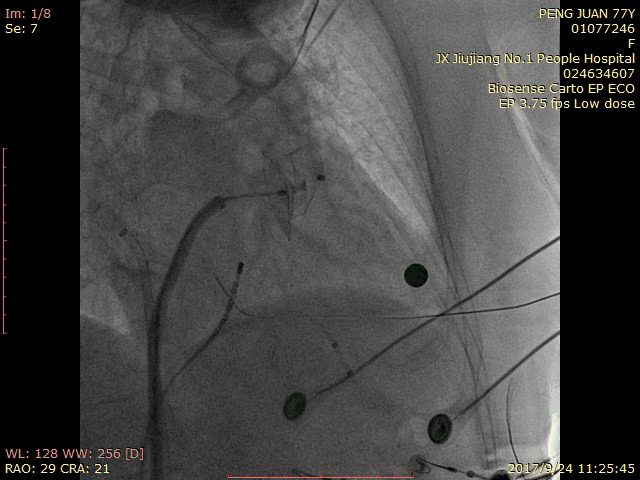

术中造影:

RAO 30 CRA 20:

RAO 30 CAU 20: